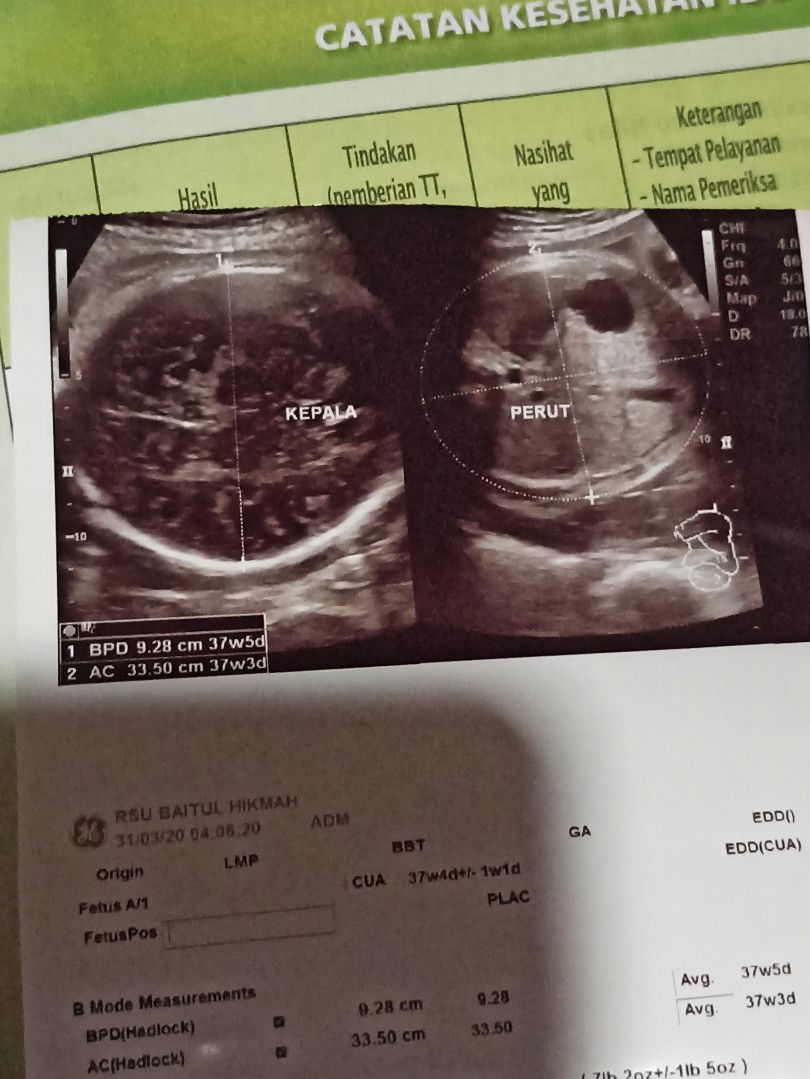

HPL labil

Trimester ketiga saya USG (11april) sempat hpl berubah dr USG di trimester pertama (20april).. Kmaren USG lgi berubah lagi sih hasilnya di tengah antara HPL trimester pertama n hpl bulan kmaren (17april) Jadi agak h2c nunggu release nya si jabang bayi? Bunda skalian Ada yg pernah kek saya...??